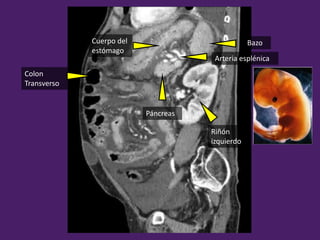

BazoCuerpo del

estómago

Páncreas

Arteria esplénica

Colon

Transverso